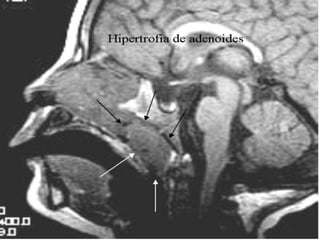

Hiperplasia de AdenóideTríadesintomática:VozhiponasalRoncosRespiração oralRinorréiapurulenta, gotejamentopós-nasal, tosse e cefaléiaFasciesadenoidiano

Hiperplasia de Adenóide- TratamentoAdenoidectomia(obstruçõesmaioresque 50% do cavum)Corticóidetópico intranasal por 6-8 semanas (ex: desonida).